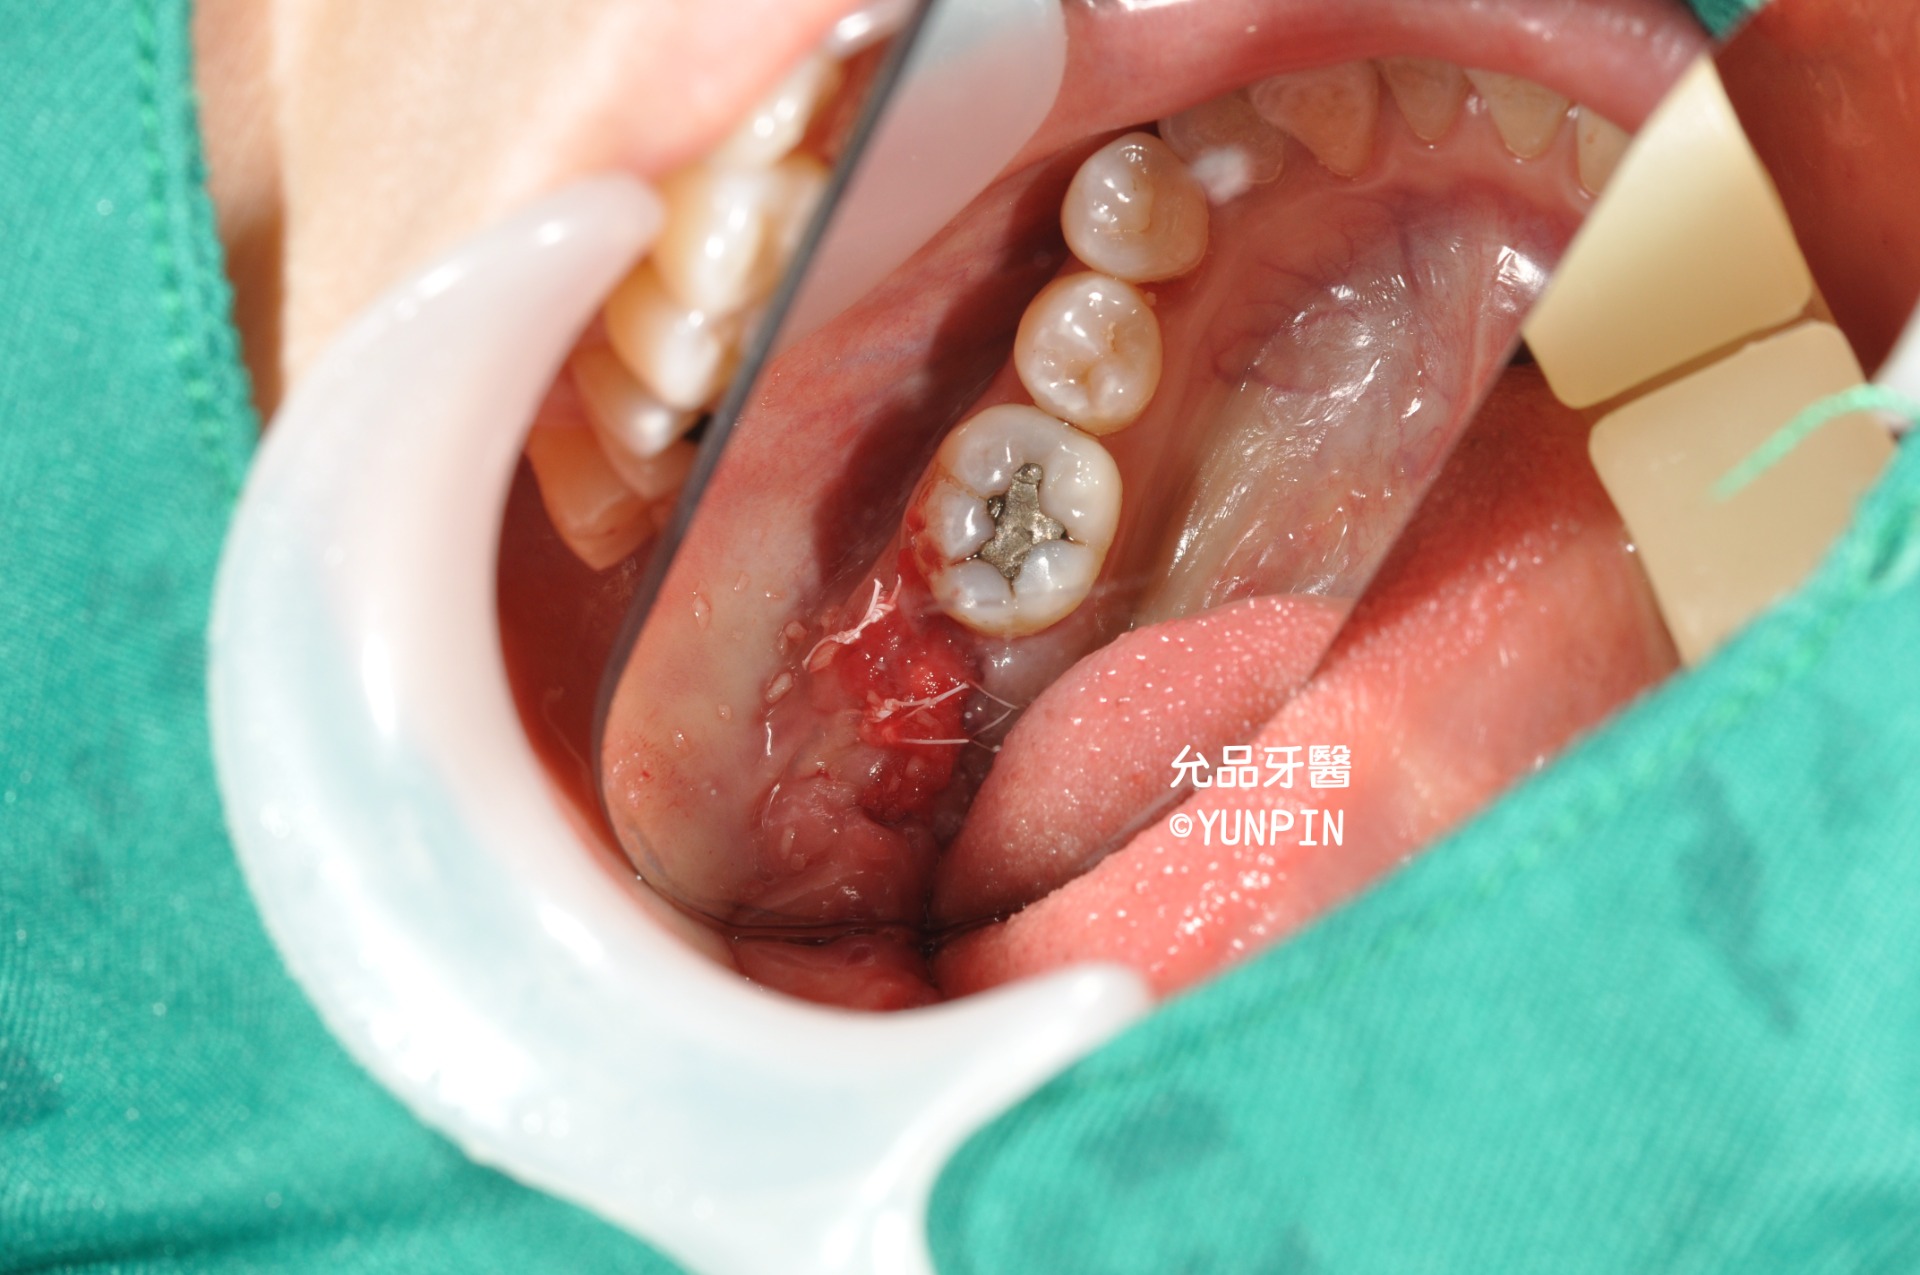

拔除後牙齒明顯斷裂

右下第二大臼齒

拔牙後牙窩